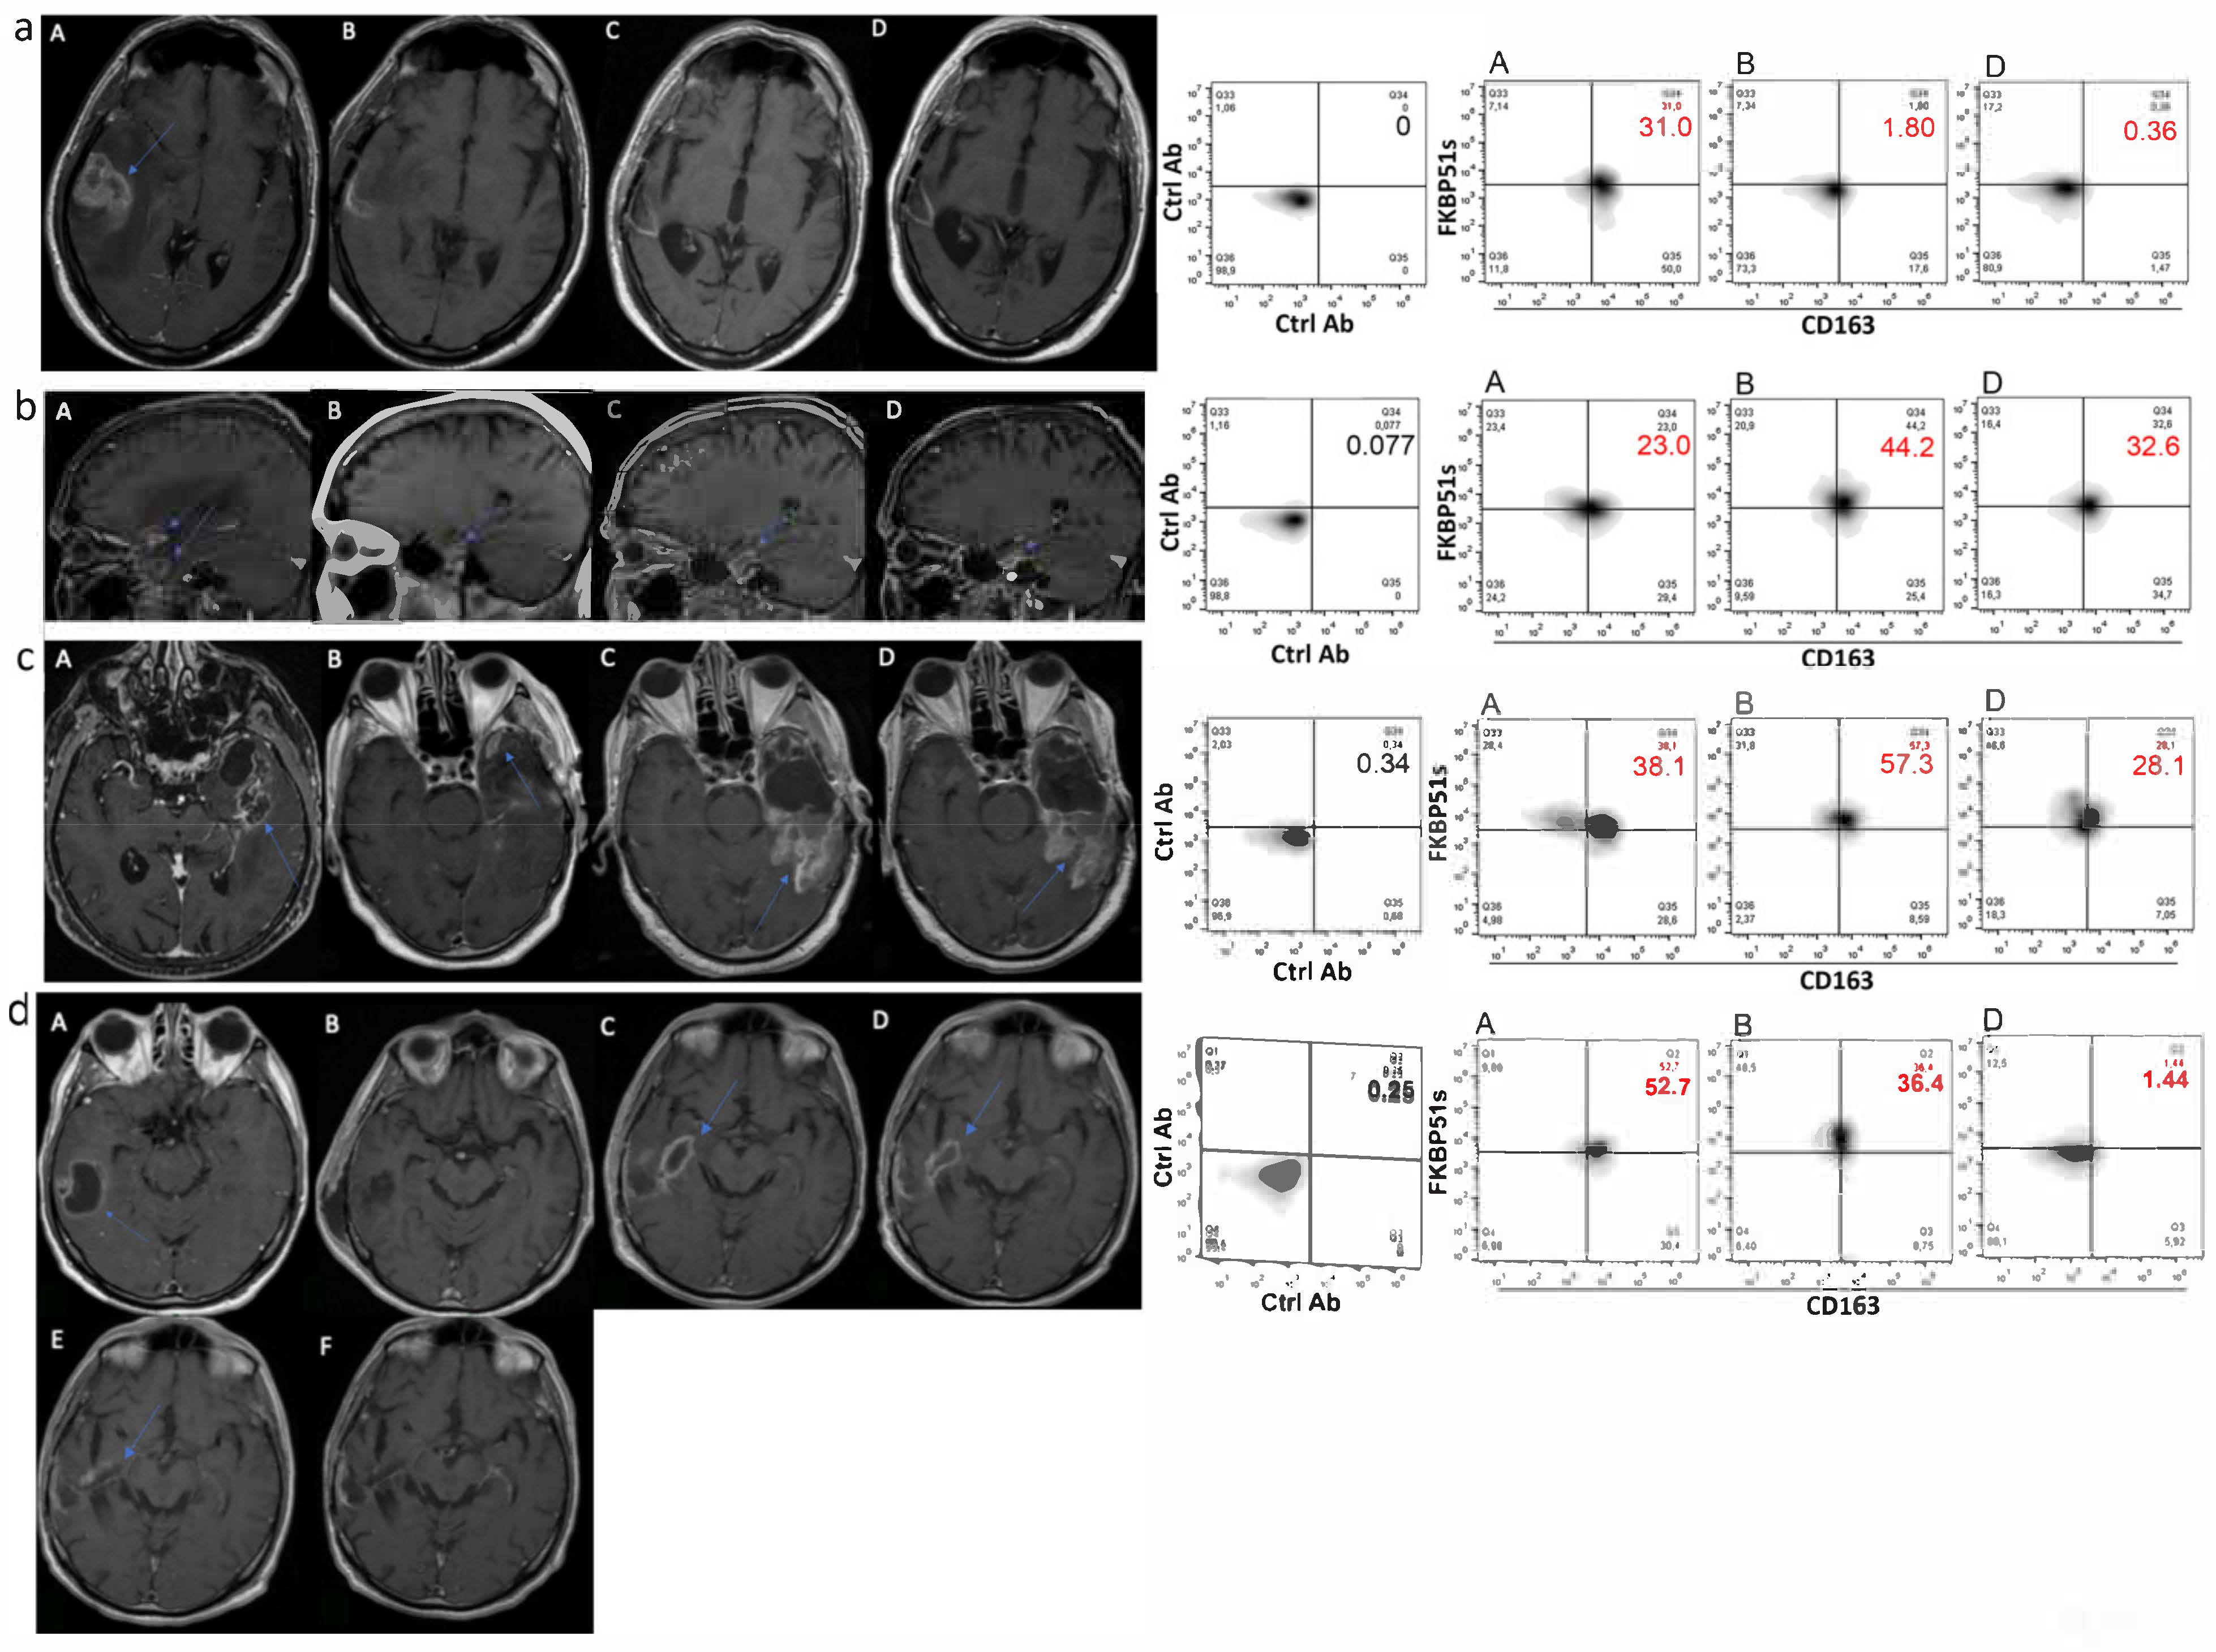

2.3. CD163+FKBP51s+ Monocytes Are Sensitive to Tumor Removal